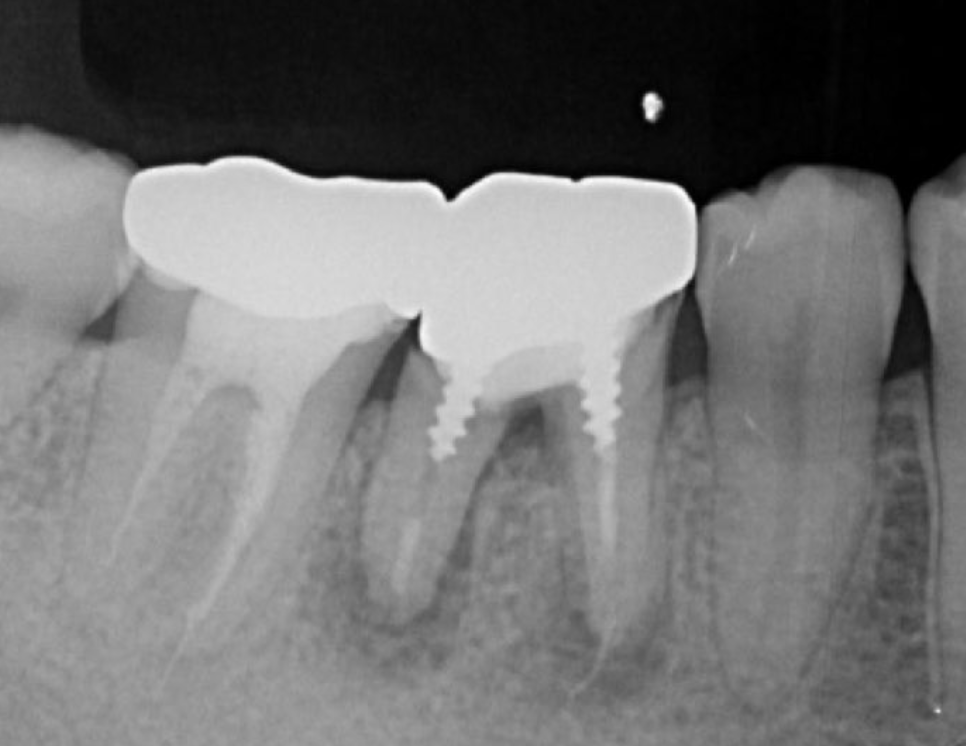

A 27-year-old female patient came to us with discomfort in the right lower jaw (Figure 1). Her primary symptoms were pain in the lower right tooth when biting and discomfort associated with not being able to chew well with the lower left single denture. The patient was married and had one young child, and previously received dental treatment in China, then had returned to Japan for childbirth and early childcare. The patient was a nonsmoker with moderate plaque control and medical history taking revealed no problems. In clinical and radiographic examinations, a root fracture was observed on tooth #46, which had been endodontic ally treated and restored with a full-cast metal crown. Periodontal probing revealed a pocket depth of 8 mm on the buccal center side of the tooth. No pain was detected with percussion and mobility of the tooth was normal. (Figure 1, Figure 2, Figure 3).

Figure 2.Pre-treatment X-ray findings. A cystic lesion was found in the mesial and distal roots apex, and root nodule of #46.